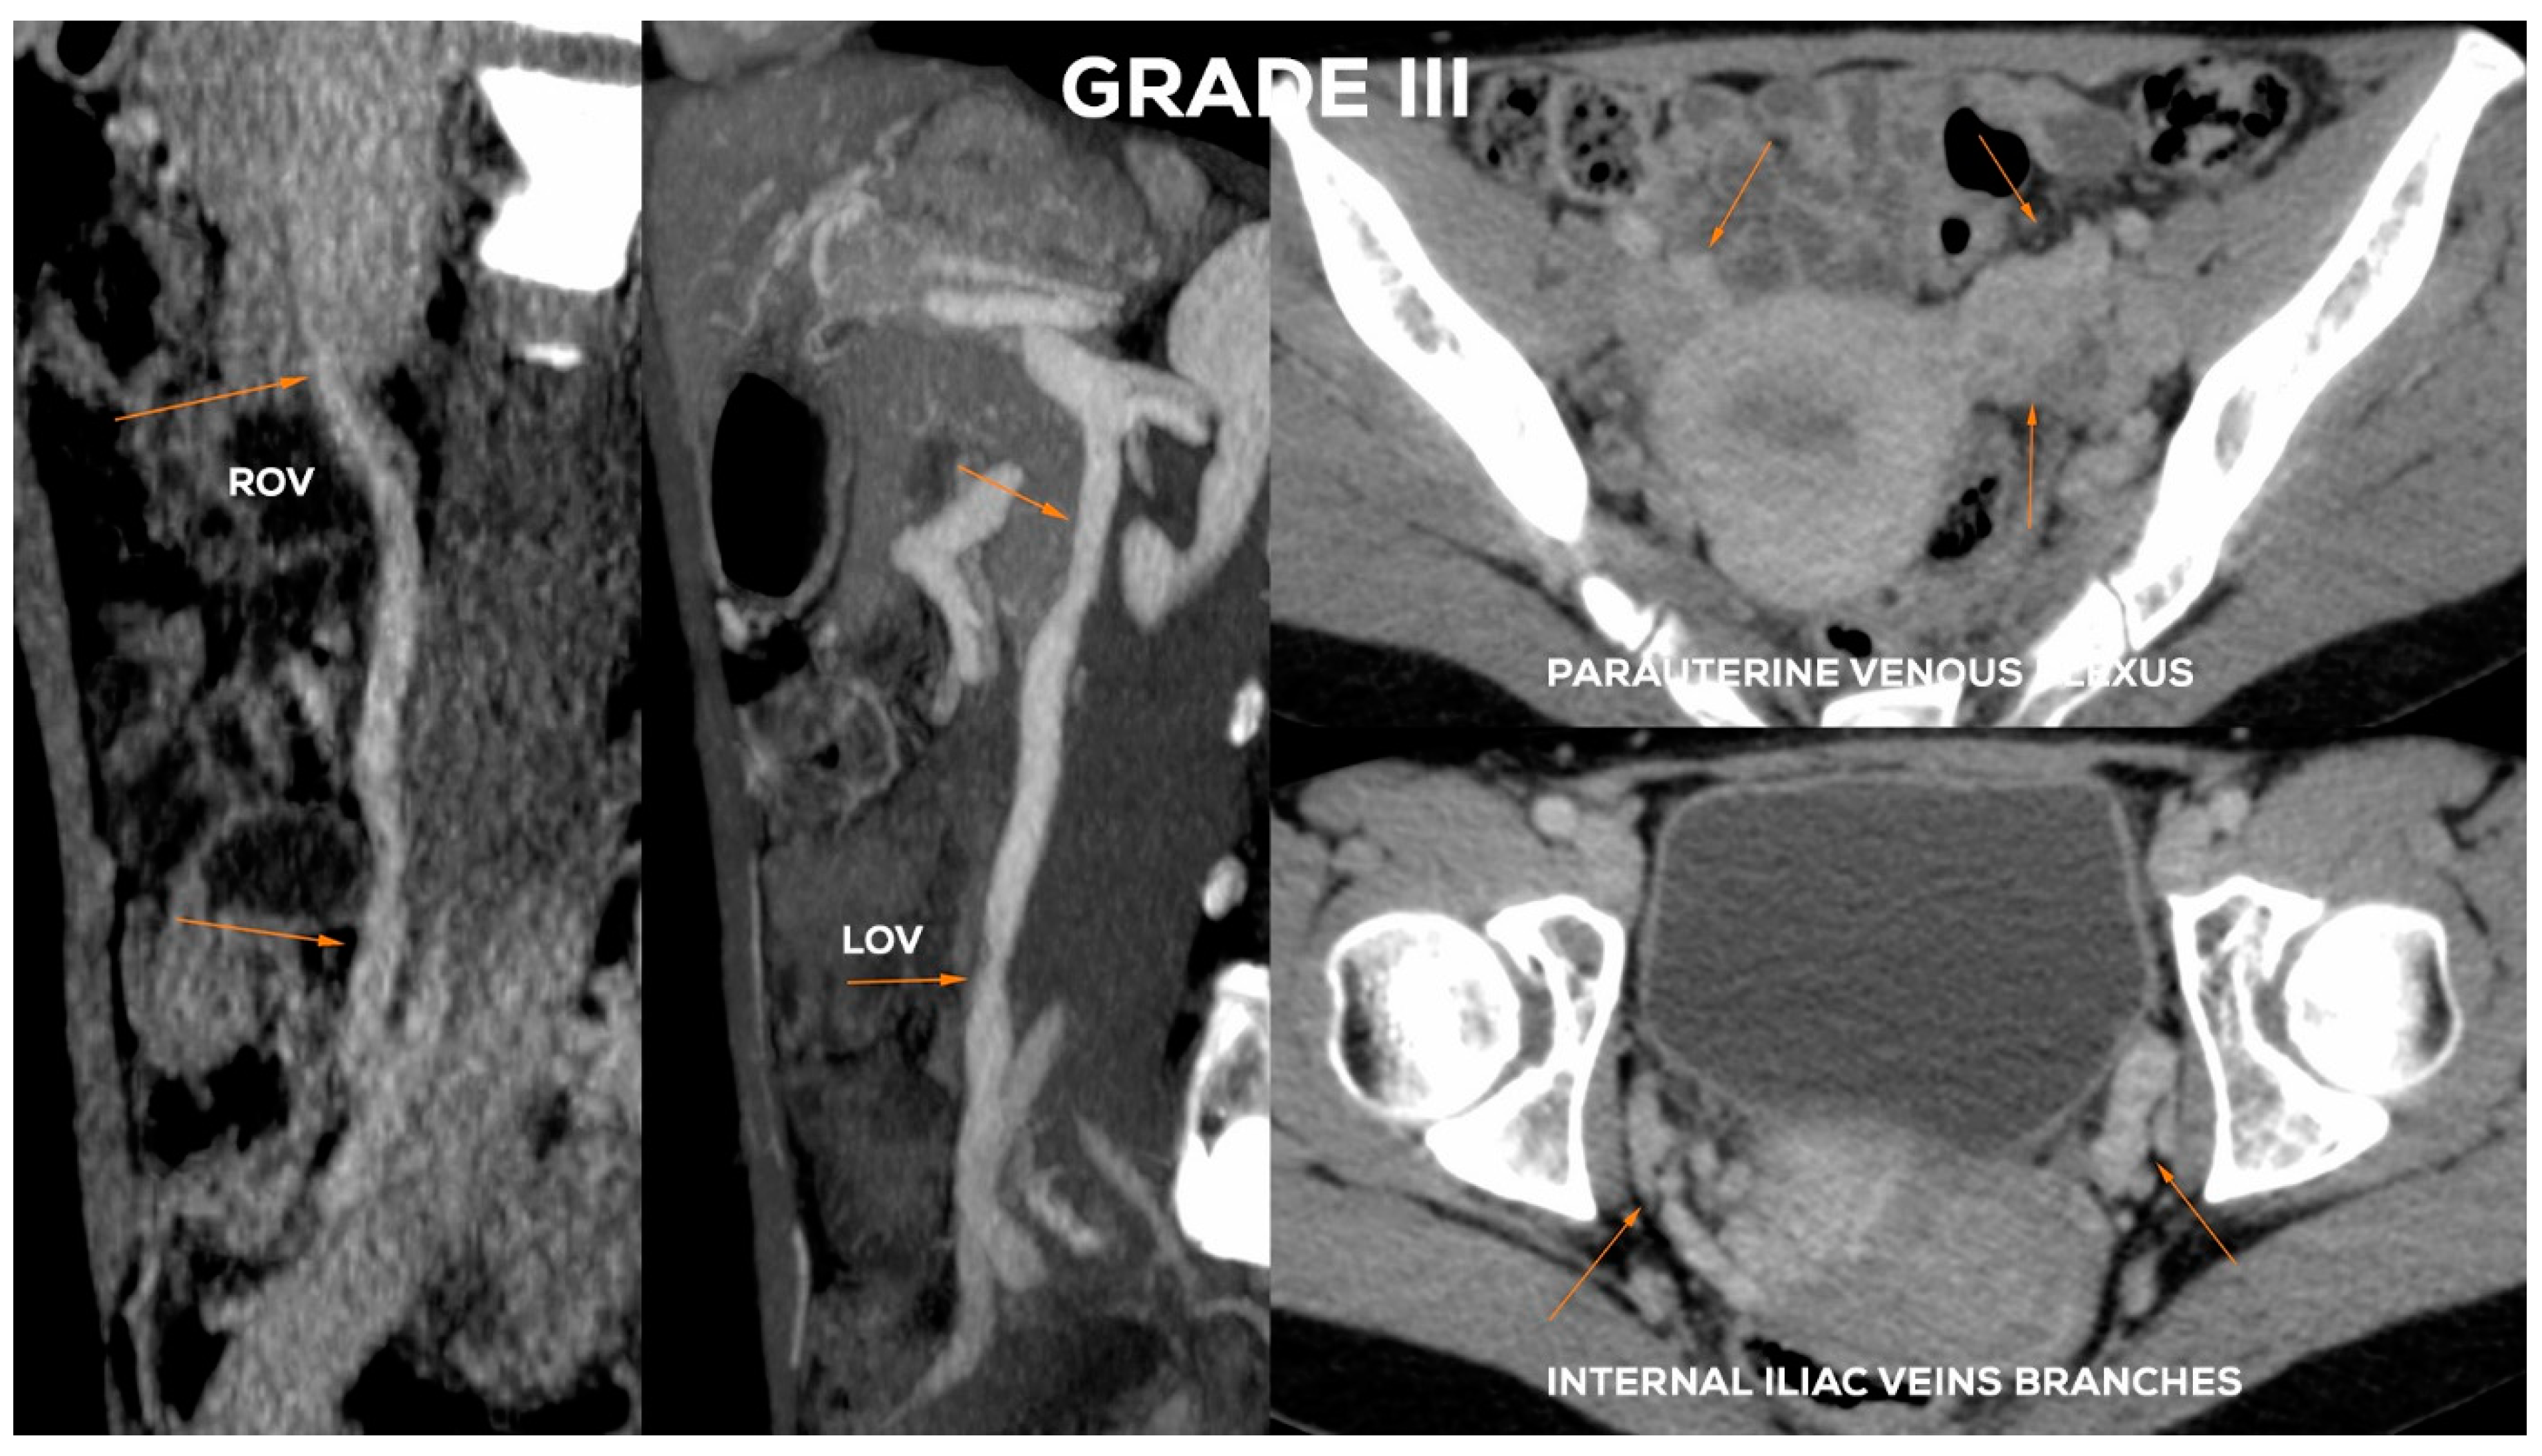

4.2.5. Grade III (GIII)

The Grade III (Figure 14) usually shows a significant expansion of the LOV trunk (ØLOV> 8 mm) with an evident distension of the ostial or sub-ostial segment. In the absence of valves, the diameter of the vessel can reach up to 10 mm. The widening of the venous plexuses of the left para-uterine region often reaches 7–8 mm. This leads to a significant overload of the uterine vein and distension of LIILV runoff (bLIILV usually widens to 7.5 mm).

In the GIII, the ROV trunk in the lower 2/3 usually reaches a diameter of 6.5–7.5 mm and is incompetent, with a relatively narrow upper segment, showing no obvious signs of insufficiency. GIII dilatation of the right para-uterine venous plexuses is usually evident (rPUV up to 6.5–7 mm). RIILV trunk and its branches (bRIILV up to 6.5 mm) are significantly overloaded (Figure 15).

Figure 15.

Typical findings in patient with Grade III ovarian veins insufficiency seen on CTV images in sagittal and axial planes.